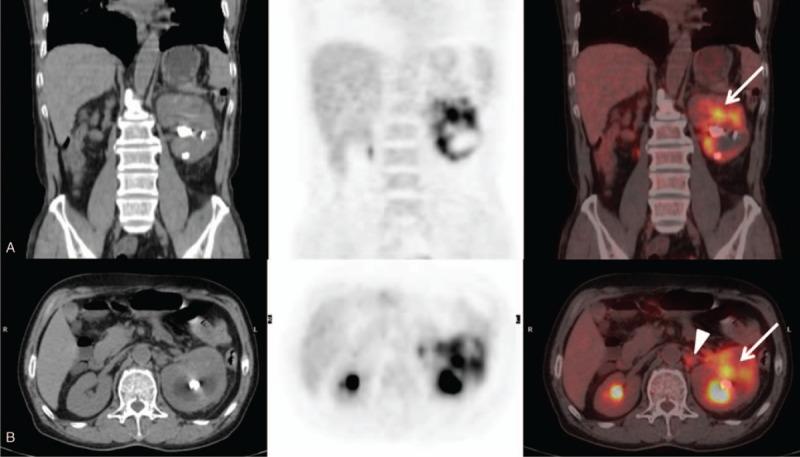

Case report of primary renal pelvis squamous cell carcinoma coexisting with long-standing calculi in left kidney on 18F-FDG PET/CT.

A 61-year-old male presented with intermittent pain at the left lumbar region for 3 days. The PET/CT images demonstrated increased F-FDG uptake in the upper pole of the left kidney and left renal hilar lymph nodes.

Pathologic examination revealed well-moderately differentiated renal pelvis SCC with lymphatic metastasis.

Our case demonstrates that F-FDG PET/CT is a useful diagnostic tool to evaluate primary renal pelvic SCC and detect metastatic lymph nodes in patients with long-standing calculi.